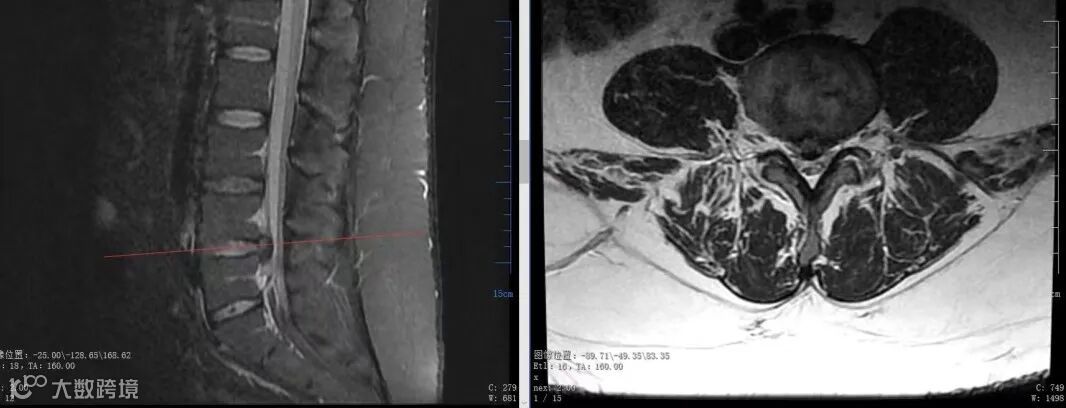

刘先生术后2天磁共振